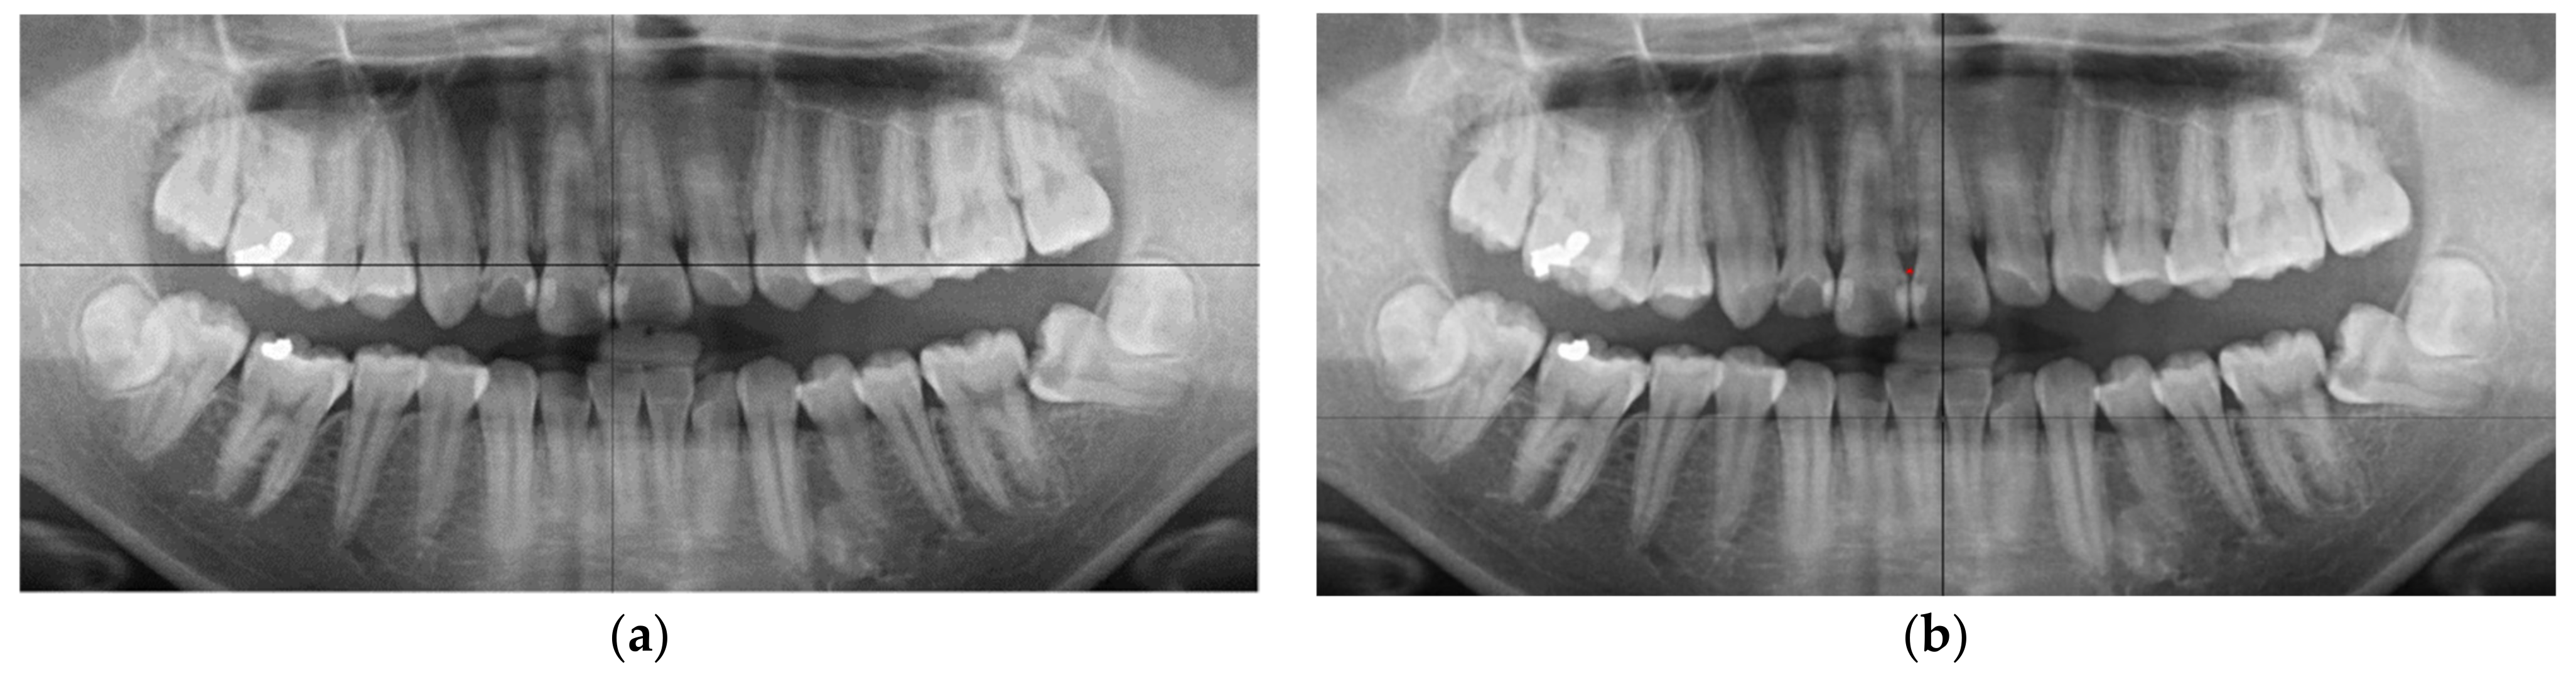

:1. Introduction

2.2. Image Segmentation

2.2.1. Curve of the Mouth

2.2.2. Curve Adjustment